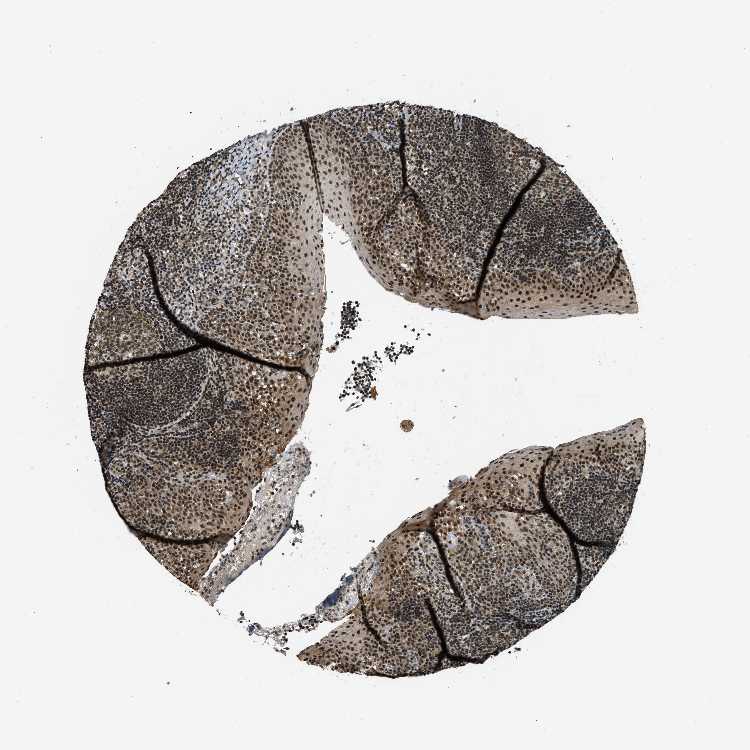

Tonsil

TONSIL - Expression summary

Protein expression

On the top, protein expression in current human tissue, based on all annotated cell types, is reported with the units not detected (n), low (l), medium (m) and high (h). Underneath, protein expression in each annotated cell type are reported using the same units.

Protein expression data is based on knowledge-based annotation. For genes where more than one antibody has been used, a collective score is set.

TONSIL - Antibody stainingi

Antibody staining in the annotated cell types in the current human tissue is reported as not detected, low, medium, or high, based on conventional immunohistochemistry profiling in selected tissues. This score is based on the combination of the staining intensity and fraction of stained cells.

Each image is clickable and will lead to virtual microscopy that enables deeper exploration of all samples and also displays staining intensity scores, fraction scores and subcellular localization as well as patient and tissue information for each sample.

Antibody HPA001656Antibody CAB017486

Germinal center cells MediumMedium

Non-germinal center cells MediumHigh

Squamous epithelial cells MediumHigh